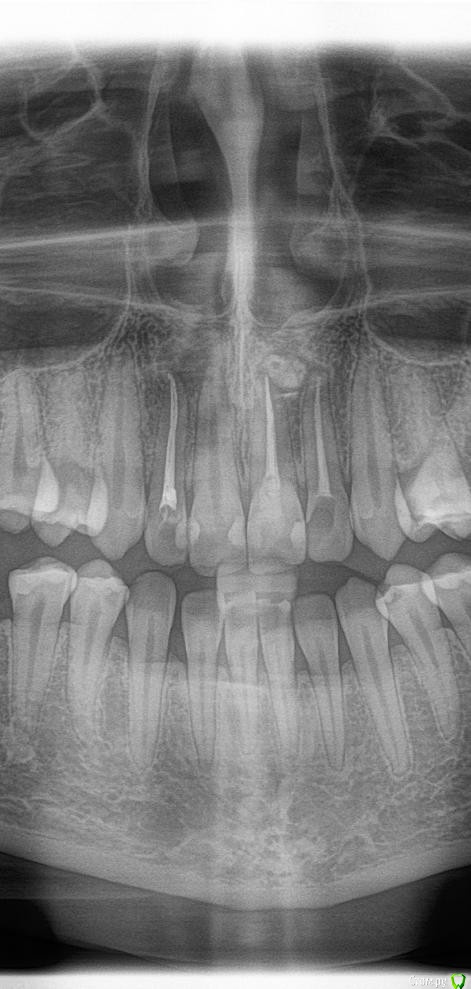

Daria_357 Опубликовано 21 августа, 2020 Поделиться Опубликовано 21 августа, 2020 Здравствуйте, резко появилась сильная неутихающая боль в 12м зубе, на третий день мне смогли оказать скорую помощь, поставив лекарство(убивающее нерв). Утром боль прошла, но опухло сильно лицо - вскрыли десну, поставив дренаж. Позже канал долго чистили и оставили временную пломбу на две недели. 18.08 приняли решение ставить постоянную пломбу. Первая пломбировка была неудачная-на снимке пломба не доходила до верхушки примерно на миллиметр. Вторая попытка закончилась так же, врач сомневалась, советовалась с коллегой, но оставила как было. На прицельном снимке видно, что не доходит в области "поворота" канала около 1мм, но у меня есть только ортопантомограмма, на ней видно только небольшую темную точку, и есть вид формы канала до пломбировки(прикрепила). По мнению врача, дойти дальше не получается так как канал изогнут. На мой вопрос почему тогда с временной пломбой пломбировка была идеальной(там пломба шла выше чем сейчас и истончалась к кончику), - врач сказала, что тогда канал был более узким, а сейчас она его расширила(?). Так же врач высказывала мнение, что если канал не запломб.до конца, то ничего страшного, - сделаем резекцию. Скажите, пожалуйста, стоит ли мне наставивать на перепломбировке уже сейчас, а не дожидаясь воспаления?Этот зуб отмечен синим. И второй вопрос по поводу плана лечения. Мне хотят с соседним передним зубом то же самое делать уже сейчас, так как есть опасения, что воспаление приблизится к нему. Верно ли это? Этот зуб отмечен красным. В этой же клинике мне года три назад вывели промбировочный материл за канал, достаточно много, но вариант, что воспаление из-за этого не подтвердили.Этот зуб отмечен зелёным. 2 Ссылка на комментарий

Daria_357 Опубликовано 5 сентября, 2020 Автор Поделиться Опубликовано 5 сентября, 2020 Здравствуйте! Подскажите, пожалуйста.Все таки было решено 11й зуб(что отмечен красным) пломбировать канал, так как на КТ сильное воспаление в полости от корня локализованное над 12 и 11, и зуб этот оказался уже мертвым. Кариеса там не было, неизвестно почему так получилось. Как вскрыли зуб - был запах, промыввали гипохлоридом,но оказалось,что мне сразу же поставили постоянную пломбу. То есть воспаление теперь будет как-то само рассасываться, т.к. шло от корня. Но я не могу совсем найти в интернете информацию о пломбирования канала сразу же постоянной, верно ли это? Ссылка на комментарий